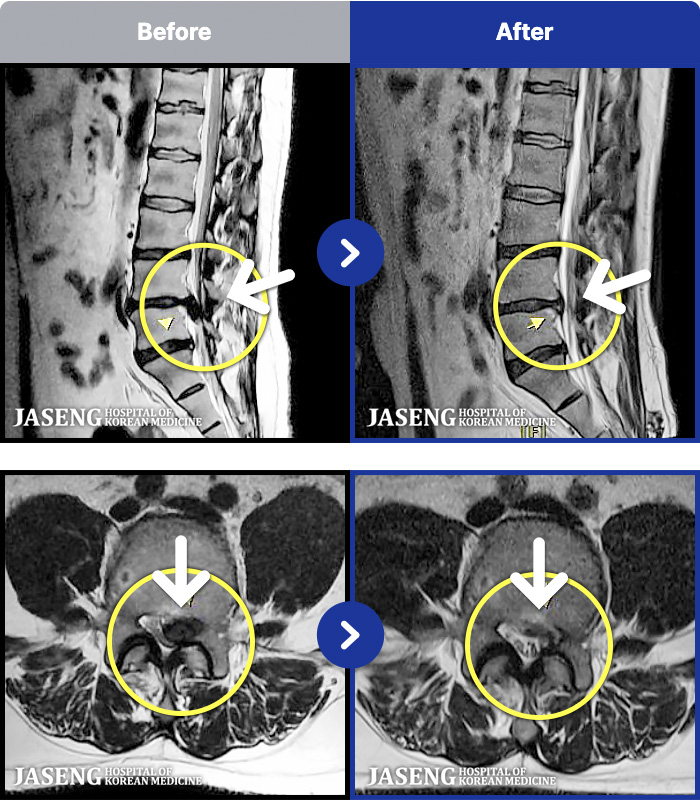

1,240 MRI ũ ʸ Ȯϼ.

MRI ġ

Ƹ ϰ ־.